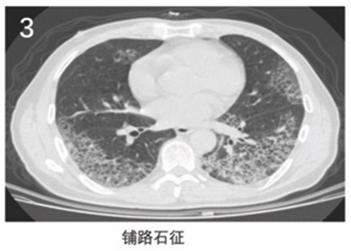

作者指出,2019新型冠状病毒肺炎有以下6个典型的CT影像学征像(图1~6):

(3)铺路石征;

(2)进展期:病灶增多、范围扩大,累及多个肺叶,部分病灶实变,磨玻璃影与实变影或条索影共存,有时会出现"铺路石征";